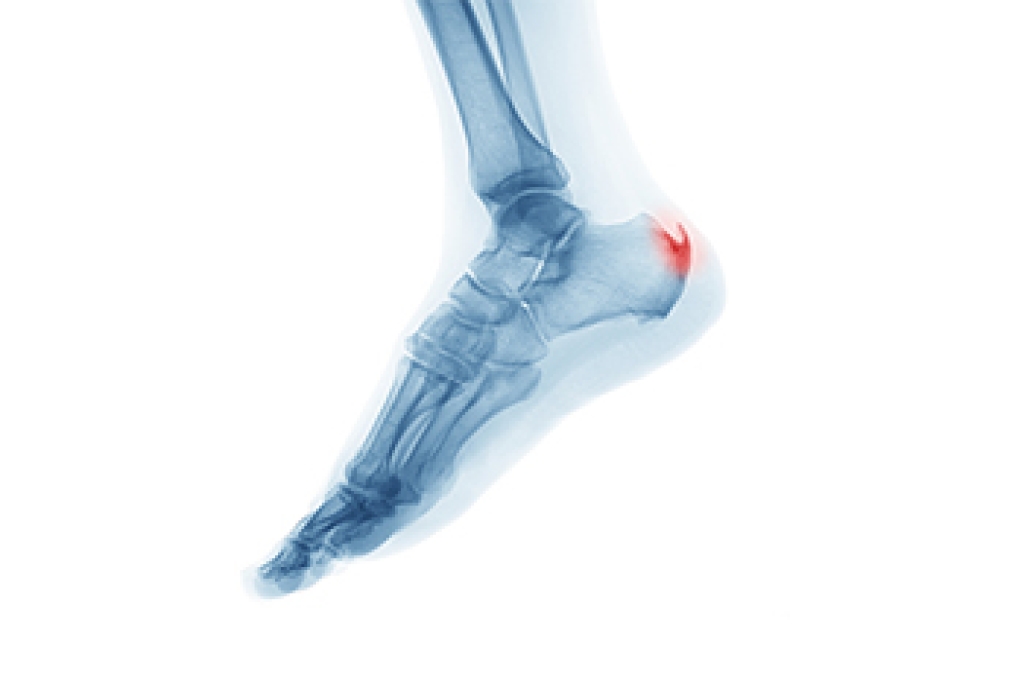

Stress fractures can be common among athletes. They can happen as a result of the consistent pressure that the bones of the feet endure during the athlete’s chosen sport. Stress fractures are defined as small, hairline fractures in the bones which may make walking and running difficult. Common symptoms can include pain surrounding the affected bone, which may improve when the foot is resting and elevated. Some patients experience bruising and swelling, accompanied by achiness. Additionally, stress fractures may gradually develop as a result of wearing shoes that do not fit properly, and this may weaken the foot bones. If you have pain in your foot, it is suggested that you consult with a podiatrist who can diagnose and treat stress fractures.

Stress fractures are the result of repetitive force being placed on the bone. Since the lower leg and feet often carry most of the body’s weight, stress fractures are likely to occur in these areas. If you rush into a new exercise, you are more likely to develop a stress fracture since you are starting too much, too soon. Pain resulting from stress fractures may go unnoticed at first, however it may start to worsen over time.

Stress fractures do not always heal properly, so it is important that you seek help from a podiatrist if you suspect you may have one. Ignoring your stress fracture may cause it to worsen, and you may develop chronic pain as well as additional fractures.